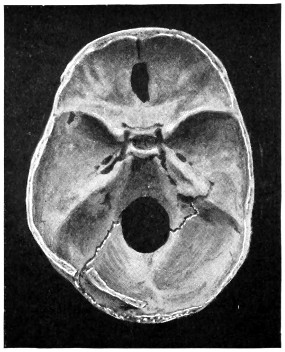

| 50 A and B. The inner aspect of the skull and the same seen on transillumination | 137 |